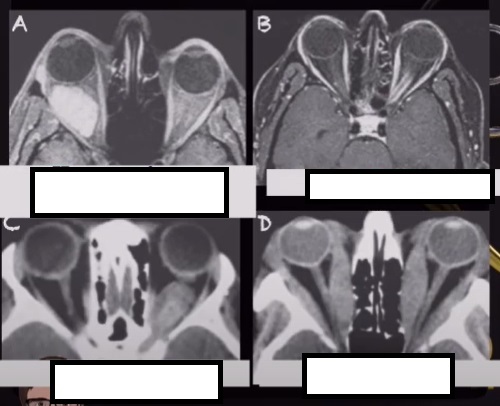

fistula carotido cavernosa